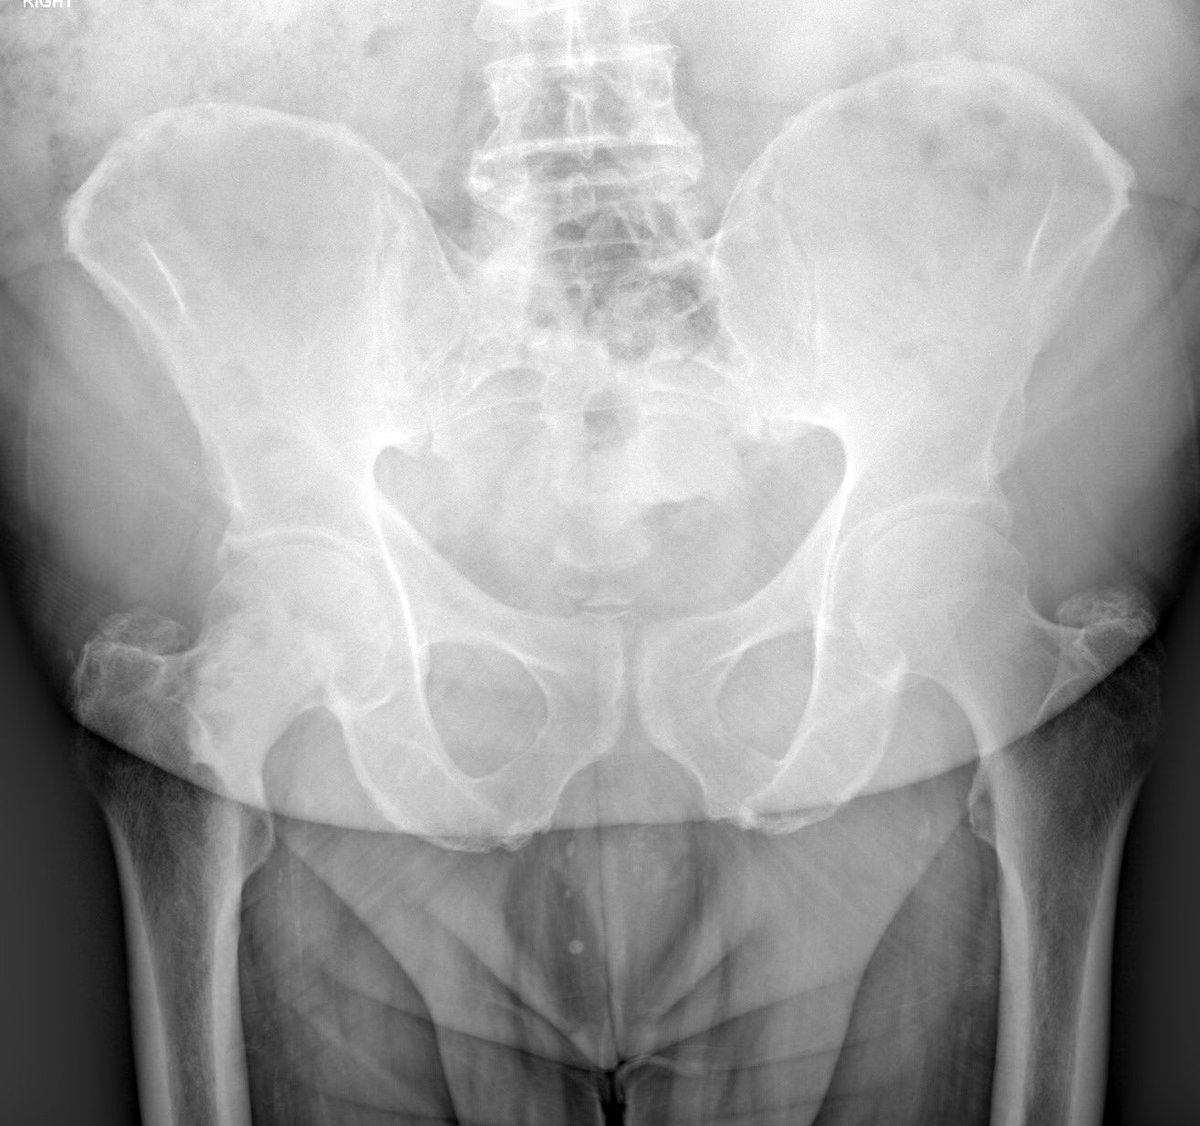

Consent ✅ Right hip pain & stiffness Both hip joints show OA changes - but R more advanced than L Why?